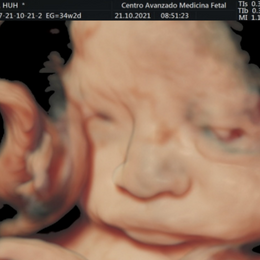

Ecografía del corazón fetal en 4D

- Las formas nuevas de ecografía pueden proporcionar imágenes en 5-D.